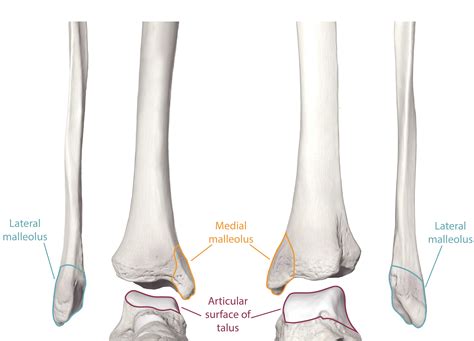

The tibia is the larger, medial bone of the lower leg, commonly known as the shinbone. It is the primary weight-bearing bone, essential for transferring force from the femur (thigh bone) to the foot. The fibula, conversely, is the thinner, lateral bone. While it does not bear significant weight, it serves a crucial role as an anchor for various muscles and stabilizes the ankle joint.

These two bones are connected along their length by a strong, fibrous membrane called the interosseous membrane. This structure keeps the bones aligned while allowing for slight movements that help absorb shock during activities like running or jumping.

• fibula tibia anatomy

• tibia and fibula skeleton